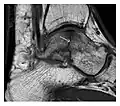

Figure 7: Fatigue fracture of the talus in a 25-year-old male basketball player with right hind foot and ankle pain, without history of trauma, and a normal initial radiograph (not shown). (a) One-month followup lateral radiograph shows normal appearance. (b) Sagittal T1-weighted MRI shows an irregular fracture line (arrow) within an ill-defined area of hypointensity corresponding to bone marrow edema.[1]